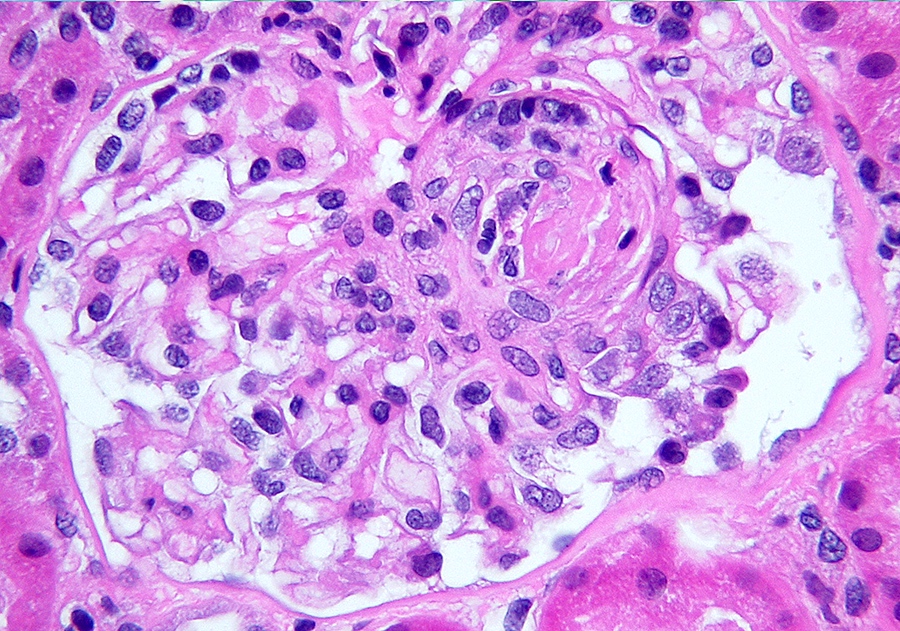

Microscopic (histologic) images

Contributed by Alexei Mikhailov, M.D., Ph.D.

- LN classes III - IV: lesions may be active (endocapillary or extracapillary proliferation) or chronic (sclerosing)

- Wire loop deposits, hyaline microthrombi, membranoproliferative lesions

- Fibrinoid necrosis and karyorrhexis may be present

- LN activity and chronicity scoring system modified in 2018 and is based on scoring of 1 (< 25% of glomeruli), 2 (25 - 50% of glomeruli) and 3 (> 50% of glomeruli) (Kidney Int 2018;93:789)

- LN activity index

- Endocapillary proliferation

- Neutrophils / karyorrhexis

- Fibrinoid necrosis (score x 2)

- Hyaline deposits

- Cellular / fibrocellular crescents (score x 2)

- Interstitial inflammation (total score 0 - 24)